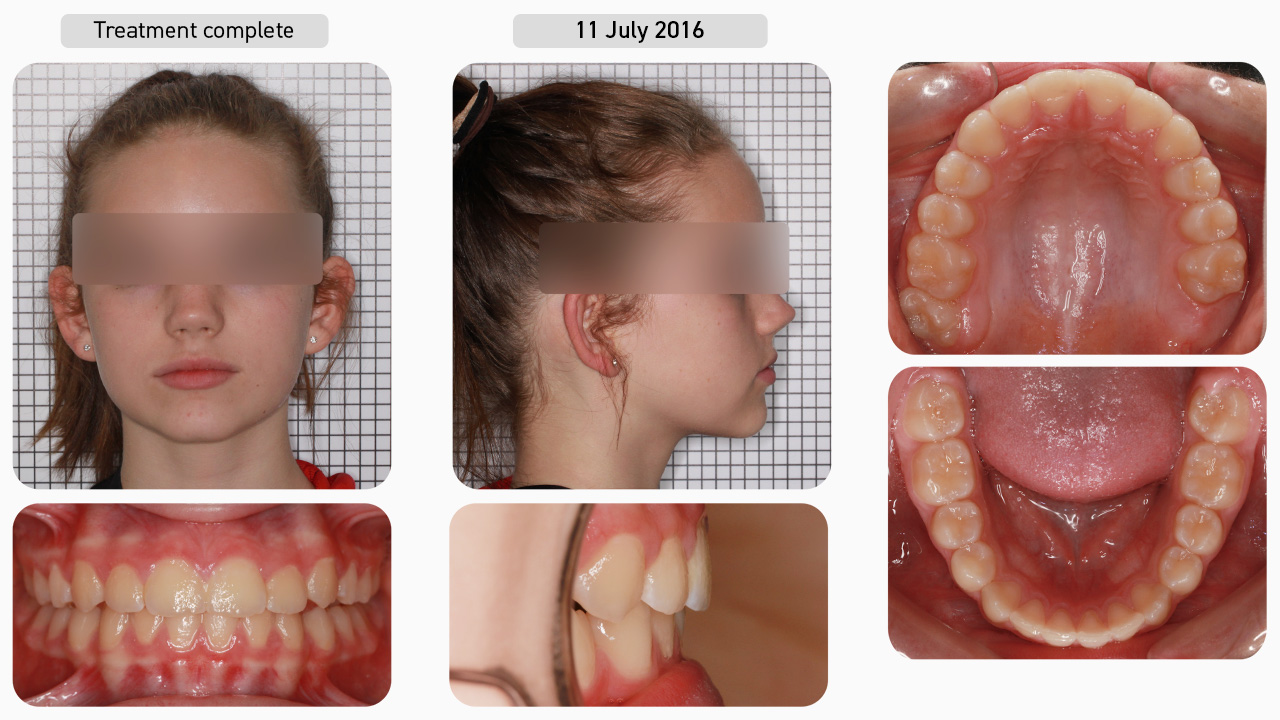

Case Study 2

This 14-year-old female patient presented with the chief complaint of crooked teeth. She was seeking a second opinion after an orthodontist recommended premolar extractions and braces. Given that her main concern was the protruding upper right canine which would “stick out” as she smiled, she wanted an improvement in the alignment of her upper front teeth without the use of braces. After being presented with the various treatment options, the decision was made to undertake Myobrace® treatment, involving the use of a series of Myobrace® appliances, the Myobrace® Activities and, given the severity of the presenting malocclusion, the use of the BWS arch expansion appliance.

Pre-treatment

Using the Myofunctional Orthodontic Evaluation (MOE) form, we documented that this patient had underdeveloped upper and lower jaws with moderate to severe dental crowding. The upper arch was severely narrow and an hourglass shape, with an almost completely blocked out upper right canine. The lower arch was also very narrow and flattened with all of the posterior teeth tipped in. There was also a deep bite and overjet. This patient was a snorer and her poor habits included mouth breathing with low tongue posture and a severe reverse swallow. Since she was in the permanent dentition, ordinarily this patient would be treated with the Myobrace® for Teens series. However, this patient preferred the K1 (large) appliance over the T1 appliance due to comfort, and so her treatment began with the Myobrace® for Kids series.

Dental Progression

She started with the K1 appliance to establish nasal breathing and begin the correction of myofunctional habits. Three months later, her breathing function had improved and, as she was consistently retaining the K1 overnight, she progressed onto the K2 (large) appliance which focuses on arch development and continued habit correction. You can already see the improvement in the arch form and the alignment of the upper and lower anterior teeth after only three months of treatment. Patients in the permanent dentition routinely require upper arch expansion to not only create space for the teeth, but more importantly, to move the teeth out of the way to facilitate correct tongue posture in the roof of the mouth. Therefore, the decision was made to use the BWS. As this must be combined with a first stage appliance, the K1 (large) was reissued to the patient.

Dental Progression

Note that after two and a half months of BWS expansion, the upper first molars started to distalise. When this occurs, the wire is removed to allow the molars to settle back and the patient was reissued the K2 appliance. Two months later, the patient was ready to enter a second round of BWS expansion to further develop the upper arch and improve function, so the K1 was reissued. Three months later, BWS expansion was complete, and the patient was issued the T2 appliance. Note the slight increase in overjet following each round of BWS expansion. This is favourable as it allows the retruded lower jaw to progressively translate forwards as the upper arch is developed.

Dental Progression

Once the arches were nicely developed and her myofunctional habits largely corrected, the patient moved on to the T3 appliance for further dental alignment and, finally, onto the T4 appliance for retention. Nine months later, we can see that her teeth have remained stable without any fixed retainers.

Treatment Complete

It is important to note that in Myobrace® treatment, we are not concerned with dental ‘perfection’ as we are looking for natural alignment of the teeth occurring in conjunction with habit correction. Once the goals of Myobrace® treatment have been achieved (establishing nasal breathing, correcting the myofunctional habits and attaining good arch forms), the patient enters into the retention phase. The T4 appliance was issued in order to retain the arch form, alignment and habits.

Facial Progression

Now that the breathing and myofunctional disorders have been corrected, the patient is no longer snoring, and improvements can be seen in the facial profile. The mandible has moved forward, the airway has improved, and the labiomental crease has shallowed as a result of correcting function.

Treatment Summary

Using the Myobrace® appliances in conjunction with the BWS arch expansion appliance and the Myobrace® Activities, we have helped the patient establish nasal breathing, correct her myofunctional habits and, therefore, achieve natural alignment of the teeth. Look at the improvement in lower anterior alignment without any fixed appliances in the lower arch, the result of correcting function. Both the upper and lower arches are broader and rounder, the deep bite has opened up, and the overjet reduced. With the correct breathing and muscle habits maintained, we expect good stability of the result.

Retention

The patient returned approximately eight months later for a retention check and the result has been maintained without the use of any fixed retainers. With the correct breathing and myofunctional habits continuing, we expect this stability to continue into the future.